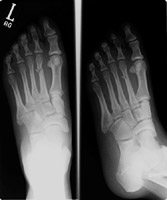

Metatarsal fractures are usually due to direct trauma. Often they are part of the Lisfranc fracture-dislocation spectrum.